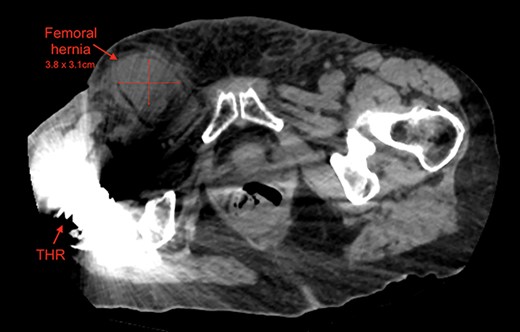

An 87-year-old Caucasian female presented to the emergency department with a 5-day history of worsening right groin pain, with an associated 2-day history of generalized malaise and fatigue. She denied fever, nausea and vomiting or signs of bowel obstruction. Her past medical history included previous right total hip replacement, type 2 diabetes mellitus and chronic renal impairment. Her vitals were normal, and examination revealed a tender right groin lump below the level of the pubic tubercle approximately 4 × 4 cm in size, with overlying erythematous skin changes. Biochemical investigation revealed a normal white cell count of 10.0 × 109/L and neutrophil profile of 7.8 × 109/L but an elevated C-reactive protein (CRP) of 190 mg/L. Contrast-enhanced computed tomography (CT) scan revealed a hypodense rounded lesion measuring 3.8 × 4.3 × 3.1 cm, medial to the right femoral vessels and extending lateral to and below the level of the pubic tubercle in the proximal anterior thigh, most consistent with a incarcerated femoral hernia (Figs. 1–3). The presence of right total hip replacement artifacts precluded accurate assessment for communication of the lesion with the peritoneal cavity.

Axial view of right femoral hernia, note the significant image distortion from the right total hip replacement beam artifacts.